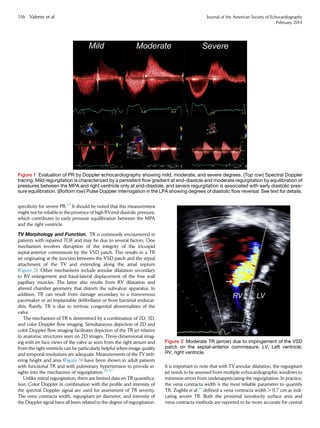

Figure 1 Evaluation of PR by Doppler echocardiography showing mild, moderate, and severe degrees. (Top row) Spectral Doppler

tracing. Mild regurgitation is characterized by a persistent flow gradient at end-diastole and moderate regurgitation by equilibration of

pressures between the MPA and right ventricle only at end-diastole, and severe regurgitation is associated with early diastolic pres-

sure equilibration. (Bottom row) Pulse Doppler interrogation in the LPA showing degrees of diastolic flow reversal. See text for details.

TV Morphology and Function. TR is commonly encountered in

patients with repaired TOF and may be due to several factors. One

mechanism involves disruption of the integrity of the tricuspid

septal-anterior commissure by the VSD patch. This results in a TR

jet originating at the junction between the VSD patch and the septal

attachment of the TV and extending along the atrial septum

(Figure 2). Other mechanisms include annular dilatation secondary

to RV enlargement and basal-lateral displacement of the free wall

papillary muscles. The latter also results from RV dilatation and

altered chamber geometry that distorts the subvalvar apparatus. In

addition, TR can result from damage secondary to a transvenous

pacemaker or an implantable defibrillator or from bacterial endocar-

ditis. Rarely, TR is due to intrinsic congenital abnormalities of the

valve.

The mechanism of TR is determined by a combination of 2D, 3D,

and color Doppler flow imaging. Simultaneous depiction of 2D and

color Doppler flow imaging facilitates depiction of the TR jet relative

to anatomic structures seen on 2D images. Three-dimensional imag-

ing with en face views of the valve as seen from the right atrium and

from the right ventricle can be particularly helpful when image quality

and temporal resolutions are adequate. Measurements of the TV teth-

ering height and area (Figure 3) have been shown in adult patients

with functional TR and with pulmonary hypertension to provide in-

sights into the mechanism of regurgitation.36,37

Unlike mitral regurgitation, there are limited data on TR quantifica-

tion. Color Doppler in combination with the profile and intensity of

the spectral Doppler signal are used for assessment of TR severity.

The vena contracta width, regurgitant jet diameter, and intensity of

the Doppler signal have all been related to the degree of regurgitation.

It is important to note that with TV annular dilatation, the regurgitant

jet needs to be assessed from multiple echocardiographic windows to

minimize errors from underappreciating the regurgitation. In practice,

the vena contracta width is the most reliable parameter to quantify

TR. Zoghbi et al.31

defined a vena contracta width  0.7 cm as indi-

cating severe TR. Both the proximal isovelocity surface area and

vena contracta methods are reported to be more accurate for central

Figure 2 Moderate TR (arrow) due to impingement of the VSD

patch on the septal-anterior commissure. LV, Left ventricle;

RV, right ventricle.